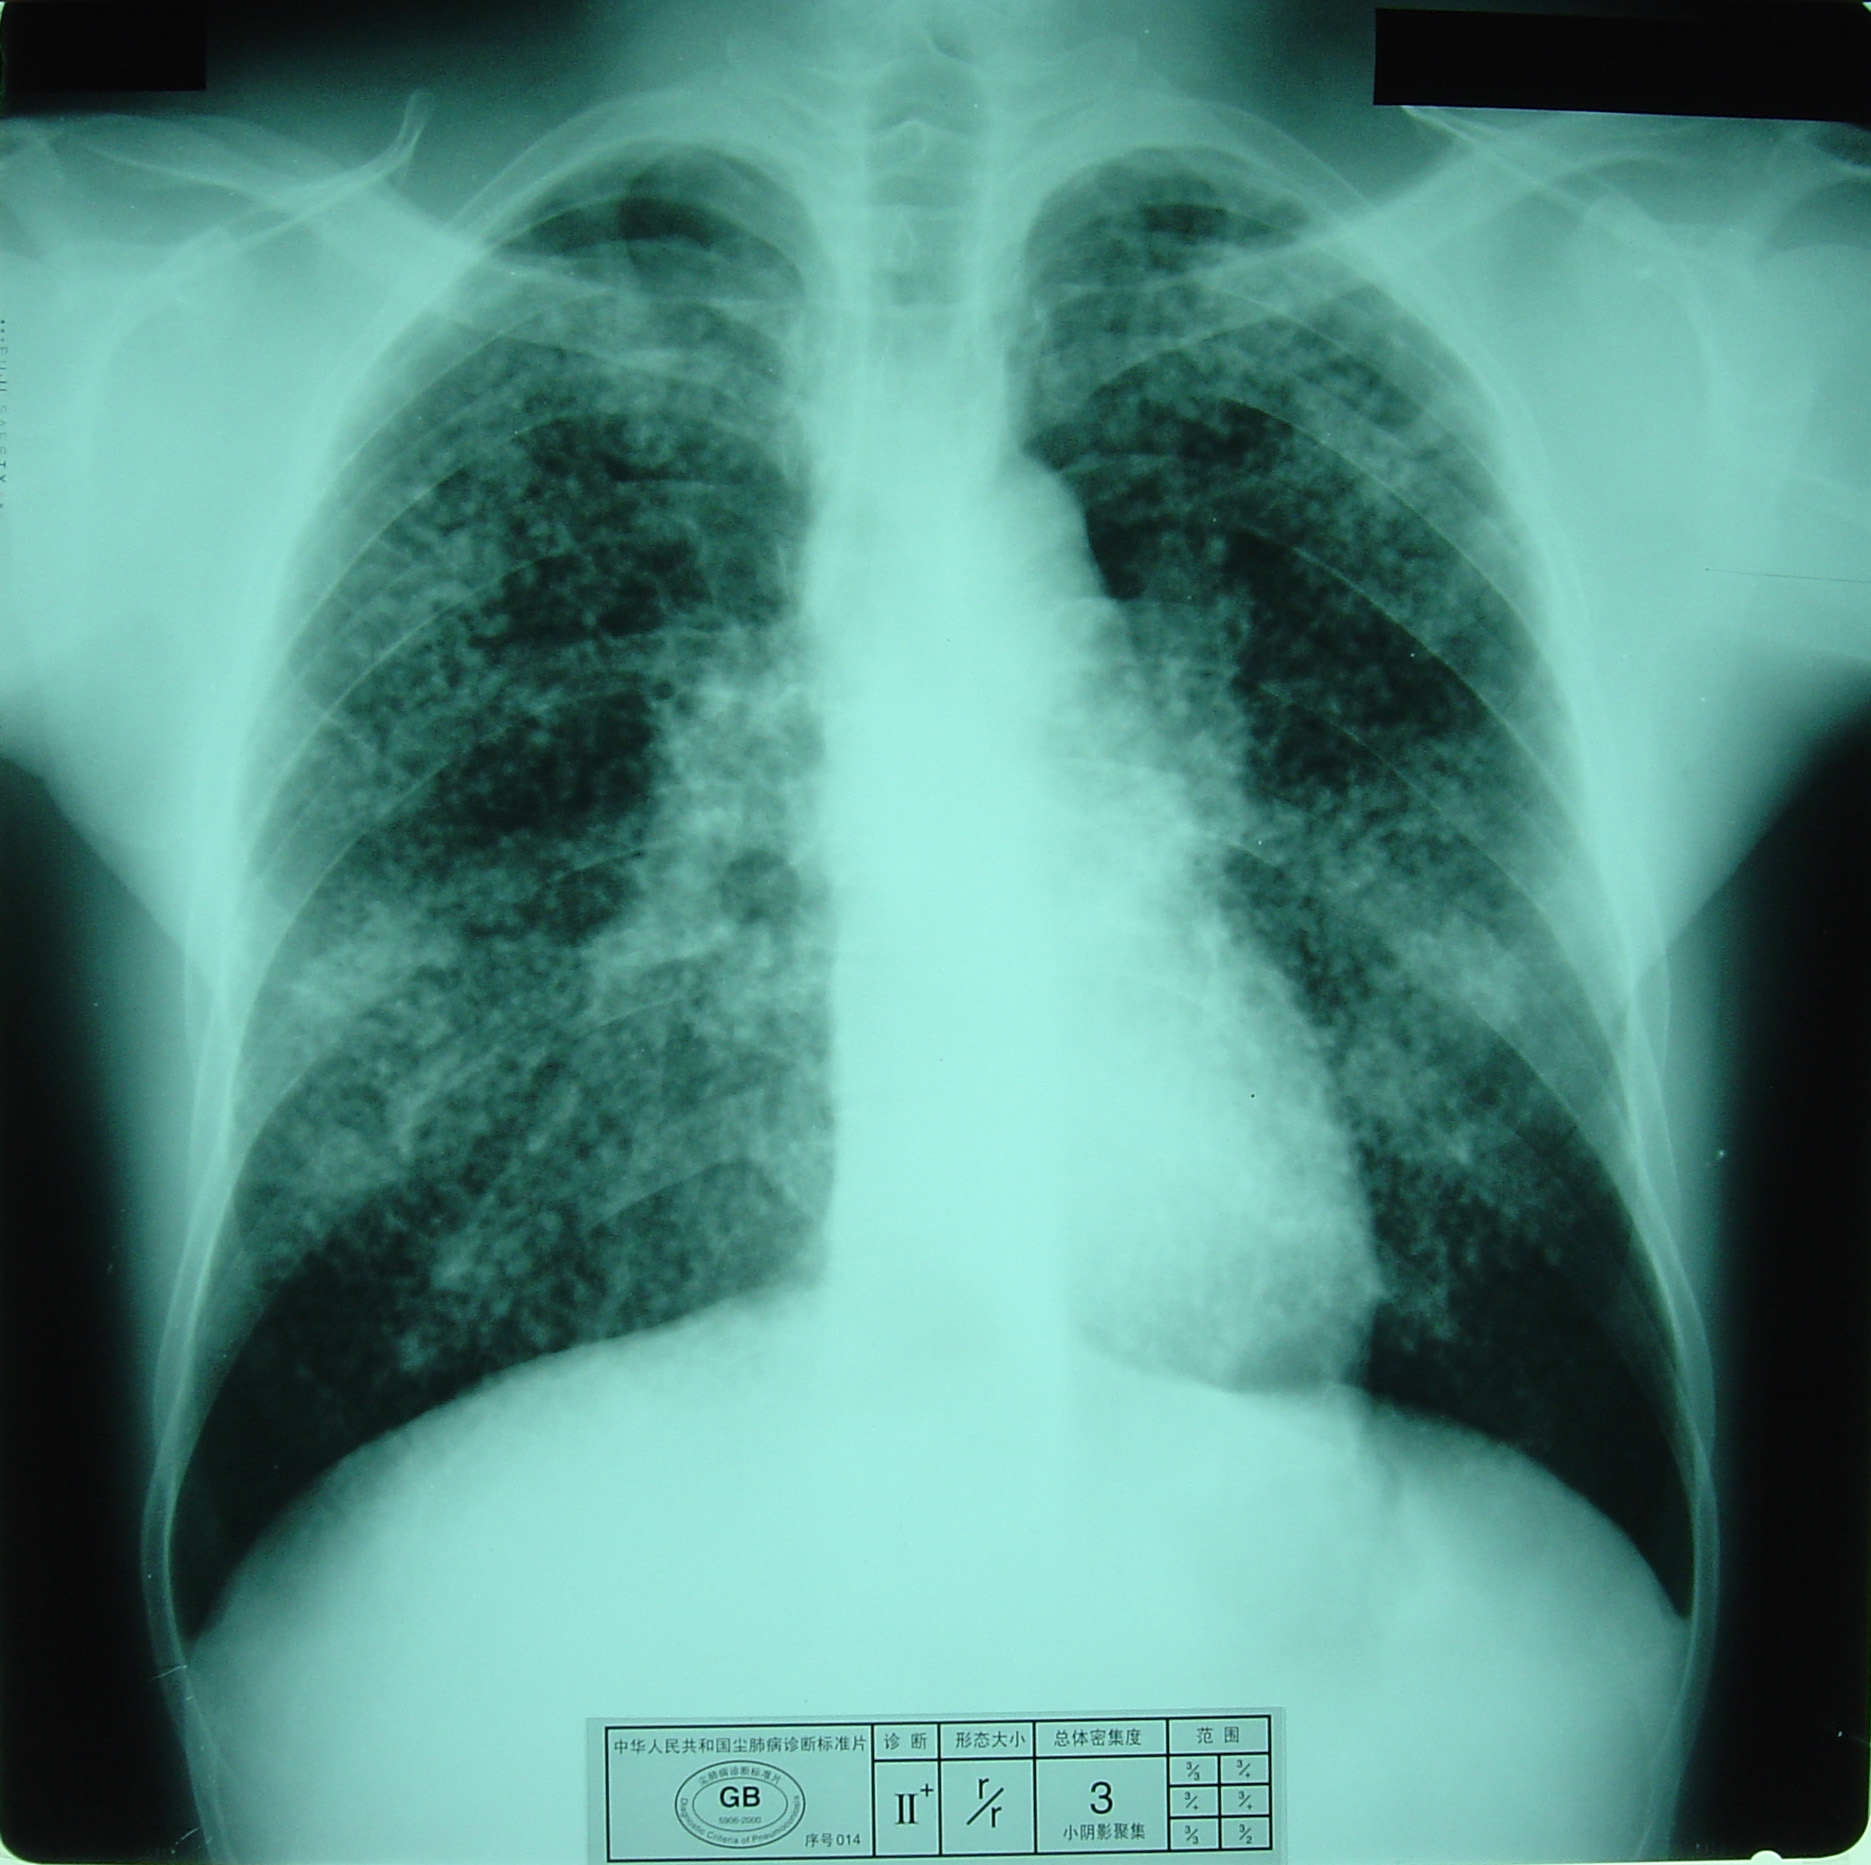

(2)X射线胸片表现:矽肺X射线胸片影像是肺组织矽肺病理形态在X射线胸片的反映,是“形”和“影”的关系,与肺内粉尘蓄积、肺组织纤维化的病变程度有一定相关关系,但由于多种原因的影响,并非完全一致。这种X射线胸片改变表现为X射线通过病变组织和正常组织对X射线吸收率的变化,呈现发“白”的圆形或不规则形小阴影,作为矽肺诊断依据。X射线胸片上其他影像,如肺门变化、肺气肿、肺纹理和胸膜变化,对矽肺诊断也有参考价值。在X射线胸片上,肺野内直径或宽度不超过10mm的阴影。小阴影按其形成分为圆形和不规则形两类。

1)圆形小阴影:是矽肺最常见和最重要的一种X线表现形态,其病理基础以结节型矽肺为主,呈圆或近似圆形,边缘整齐或不整齐,直径小于10mm,按直径大小分为p(<1.5mm)、q(1.5~3.0mm)、r(3.0~10mm)三种类型。p类小阴影主要是不太成熟的矽结节或非结节性纤维化灶的影像,q、r类小阴影主要是成熟和较成熟的矽结节,或为若干个小矽结节的影像重叠。圆形小阴影早期多分布在两肺中下区,随病变进展,数量增多,直径增大,密集度增加,波及两上肺区。

圆形小阴影(r类小阴影)

3)尘肺叁期:有下列表现之一者:

a) 有大阴影出现,其长径不小于20mm,短径不小于10mm;

b)有总体密集度为3级的小阴影,分布范围超过4个肺区并有小阴影聚集;

c) 有总体密集度为3级的小阴影,分布范围超过4个肺区并有大阴影。

尘肺叁期

尘肺叁期

尘肺叁期